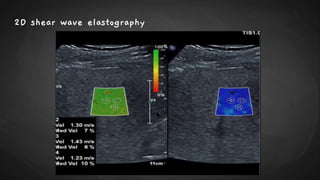

2D shear wave elastography